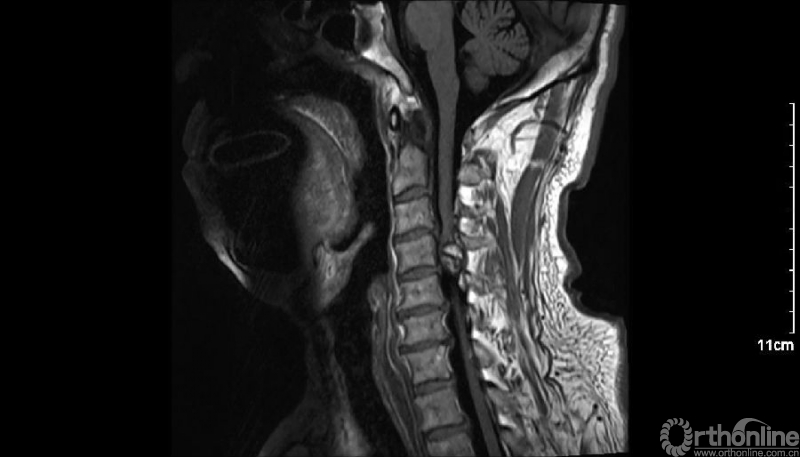

入院查体患者四肢肌张力高,双侧hoffman阳性。CT及MRI检查提示C4/5左侧关节突内缘有一巨大骨块(15mm*16mm),相应节段椎管严重狭窄。椎管内骨块的前端还有一游离骨块。

影像学资料